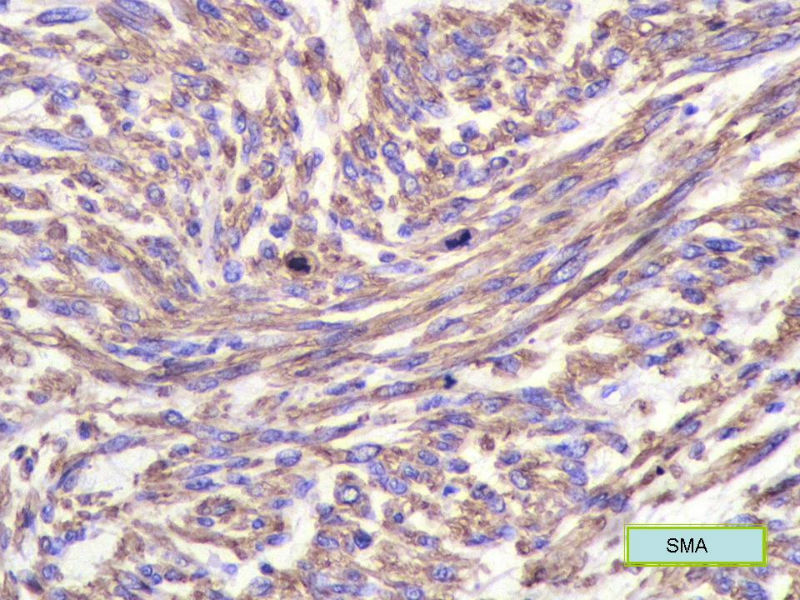

女,71岁,胸闷2月余,CT提示纵膈占位。手术见左肺与胸膜之间有一肿块,与周围粘连,手术切除。肉眼,肿块7X5X3厘米,边界较清楚,切面灰白灰红,质韧。

镜检:核分裂5</10HP

• 纵膈占位,新加免疫组化图1

图1

• 纵膈占位,新加免疫组化图2

图2

此例我们诊断为平滑肌肉瘤,因为很少见,请各位老师讨论!

形态学和免疫组化标记符合平滑肌肉瘤,但要标记Myogenin等鉴别横纹肌肉瘤,标记D2-40、Calretinin等鉴别肉瘤样间皮瘤。